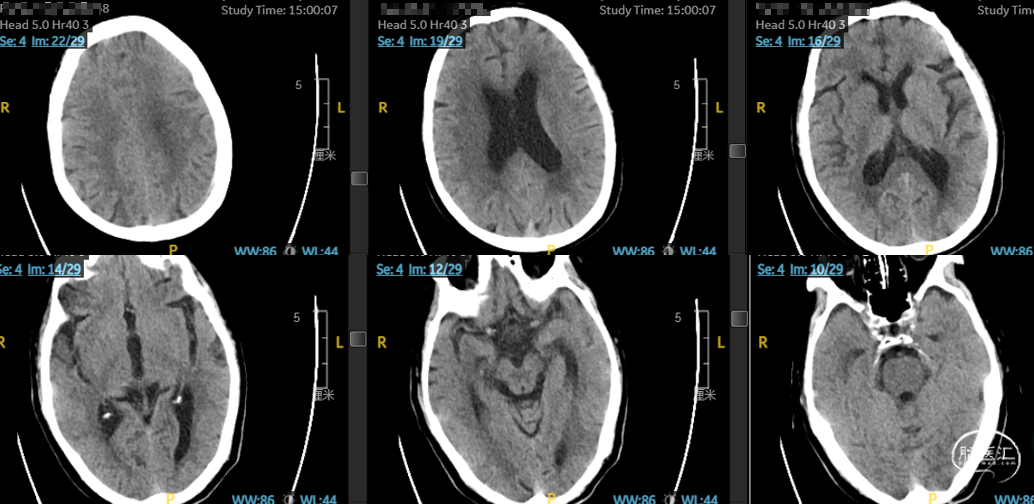

影像信息

CT平扫未见明显缺血性。

CT平扫(ASPECT评分及CTP灌注)。